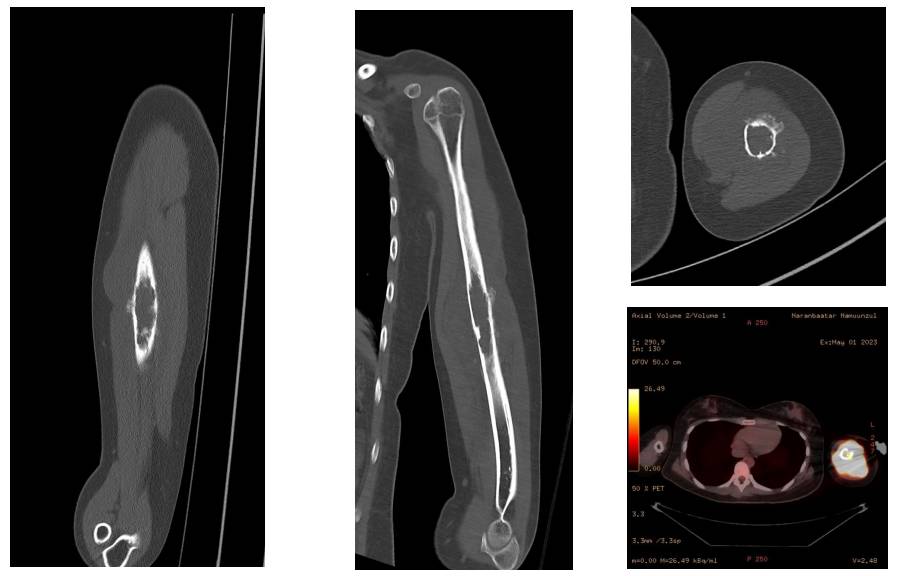

Ameliyat Öncesi: Tomografide ciddi yıkım, düzensizlik ve periost reaksiyonu, PET’de yoğun artmış aktivite görülmekte